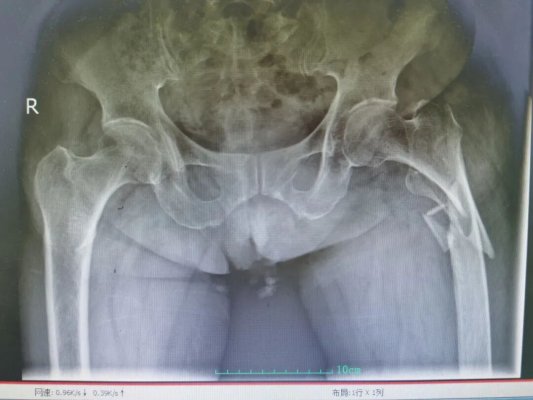

极限挑战!101岁、35Kg超高龄骨折 青大附院平度院区创造生命奇迹

“少怕噎,老怕摔”,这句俗语在101岁的綦奶奶(化名)身上得到了沉重印证。